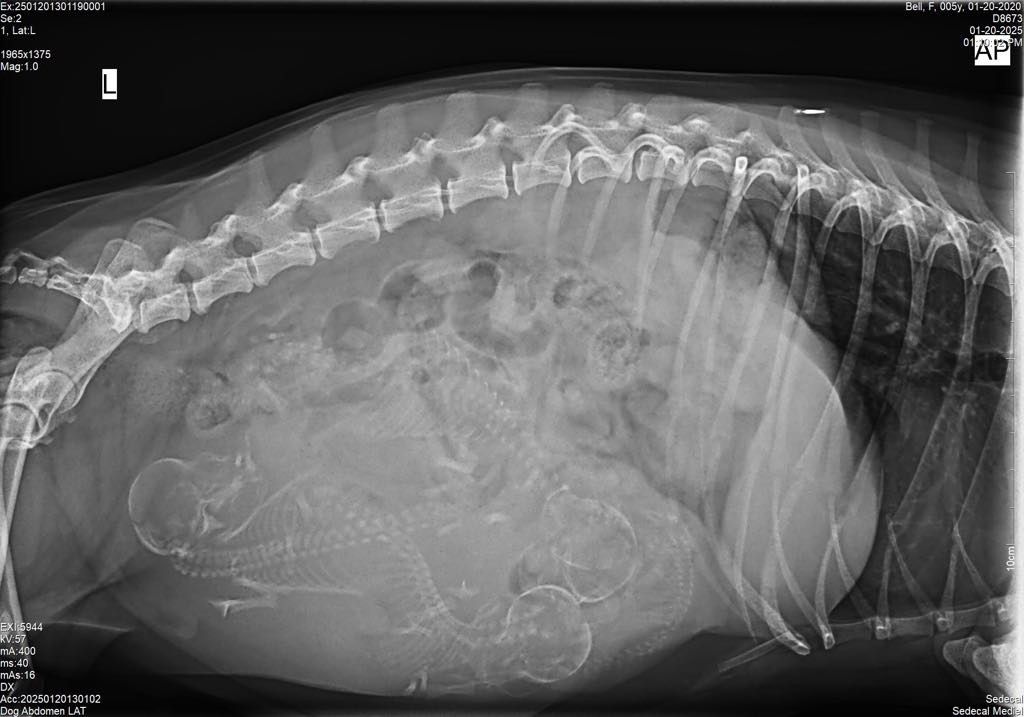

Röntgenundersökning

- Vårt digitala röntgensystem ger högkvalitativa bilder på kort tid. Vi kan identifiera skador som frakturer, ledproblem eller sjukdomar i lungor och hjärta.

- Särskilt användbart vid misstanke om främmande föremål som har svalts, då vi snabbt kan lokalisera och planera en säker åtgärd.

- Kontrollera dräktighet och följa fostrets utveckling.